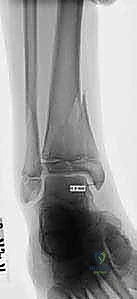

- الأشعة السينية (X-rays): هي الخطوة الأولى والأساسية. يتم التقاط صور من زوايا متعددة (أمامية، جانبية، ومائلة) لتقييم الكسر.

- الأشعة المقطعية ثلاثية الأبعاد (3D CT Scan): تُعد ضرورة حتمية في حالات كسور تيلوكس والكسور ثلاثية المستويات، أو أي كسر يمتد داخل المفصل. توفر الأشعة المقطعية خريطة دقيقة لحجم القطع العظمية ومقدار التباعد (Displacement)، مما يساعد في التخطيط الجراحي المسبق.

- كسر تيلوكس للمراهقين (Juvenile Tillaux Fracture): هو كسر من النوع الثالث لسالتر-هاريس، يحدث في الجزء الأمامي الوحشي (الخارجي) من قصبة الساق. يحدث عندما يكون الجزء الإنسي من لوح النمو قد أغلق، بينما الجزء الوحشي لا يزال مفتوحًا، فيقوم الرباط (AITFL) بانتزاع هذه القطعة.

- الكسر ثلاثي المستويات (Triplane Fracture): كسر شديد التعقيد يمر عبر ثلاثة مستويات مختلفة (سهمي، إكليلي، وعرضي). يظهر في الأشعة الأمامية ككسر سالتر-هاريس من النوع الثالث، وفي الأشعة الجانبية ككسر من النوع الثاني. يتطلب هذا الكسر دائمًا فحصًا مقطعيًا (CT Scan) لتقييمه بشكل صحيح.